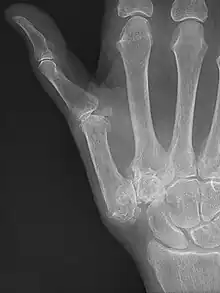

Joint replacement

X-ray of trapeziometacarpal joint replacement. Left hand of a 58-year-old woman.

The joint can be replaced with artificial material. An artificial joint is also referred to as a prosthesis. Prostheses are more problematic at the trapeziometacarpal joint compared to joints like the knee or the hips.

[23]Prostheses come in many varieties, such as spacers or resurfacing prostheses.

It's not clear within the current literature that a prosthesis has any advantage over trapeziectomy.[23]

Overall, joint replacements are related to long-term complications such as subluxation, fractures, synovitis (due to the material used) and nerve damaging.In many cases revision surgery is needed to either remove or repair the prosthesis. Also note that usage of a joint replacement is heavy in costs.

The quality of the prostheses is improving and there is reason to believe this will have a positive effect on outcome in the years to follow.[23]